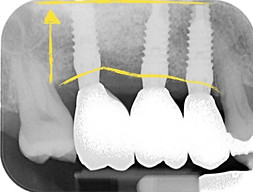

Linee gialle mostrano come l'osso si sia riassorbito nel tempo rispetto alla linea verde che è il nostro target rigenerativo

Radiografia dell'osso rigenerato con membrane rinforzate in titanio